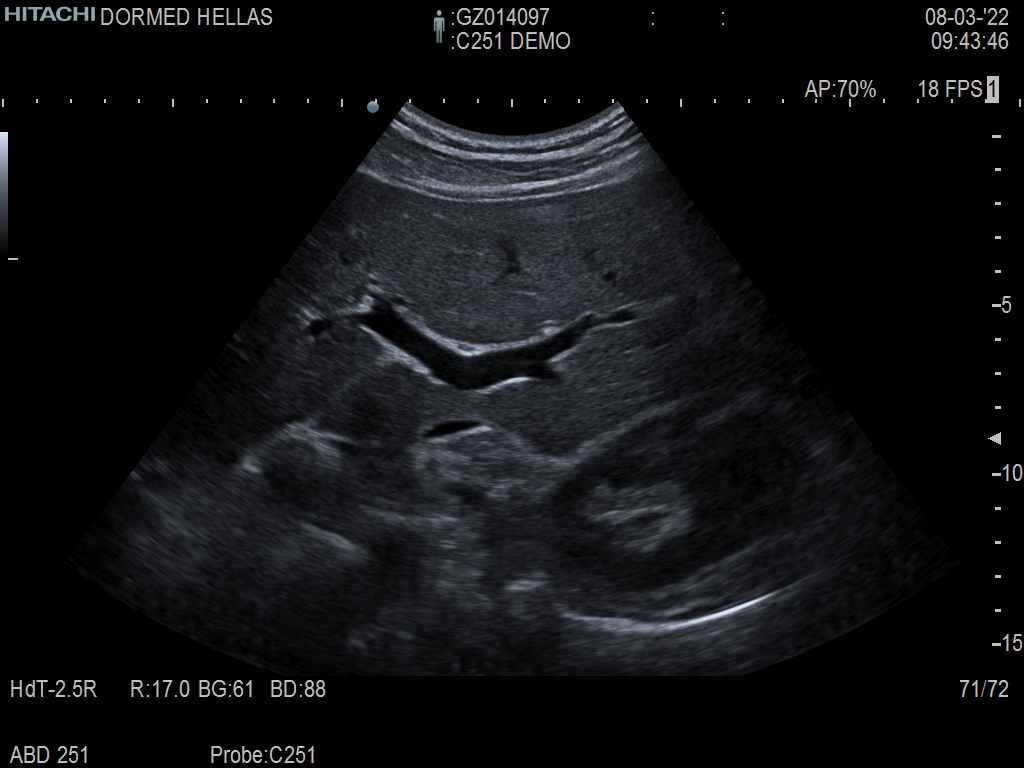

Hitachi C251 Ref Abdominal Convex – ARIETTA

ARIETTA Convex C251 Abdominal

Hitachi C251 Abdominal Convex – ARIETTA

Frequency Range: 5 – 1 MHz

Scan Width: 50 mm Radius

Scan Angle: 70° FOV

Hitachi C251 Abdominal Convex – ARIETTA for Abdominal and Women’s Health